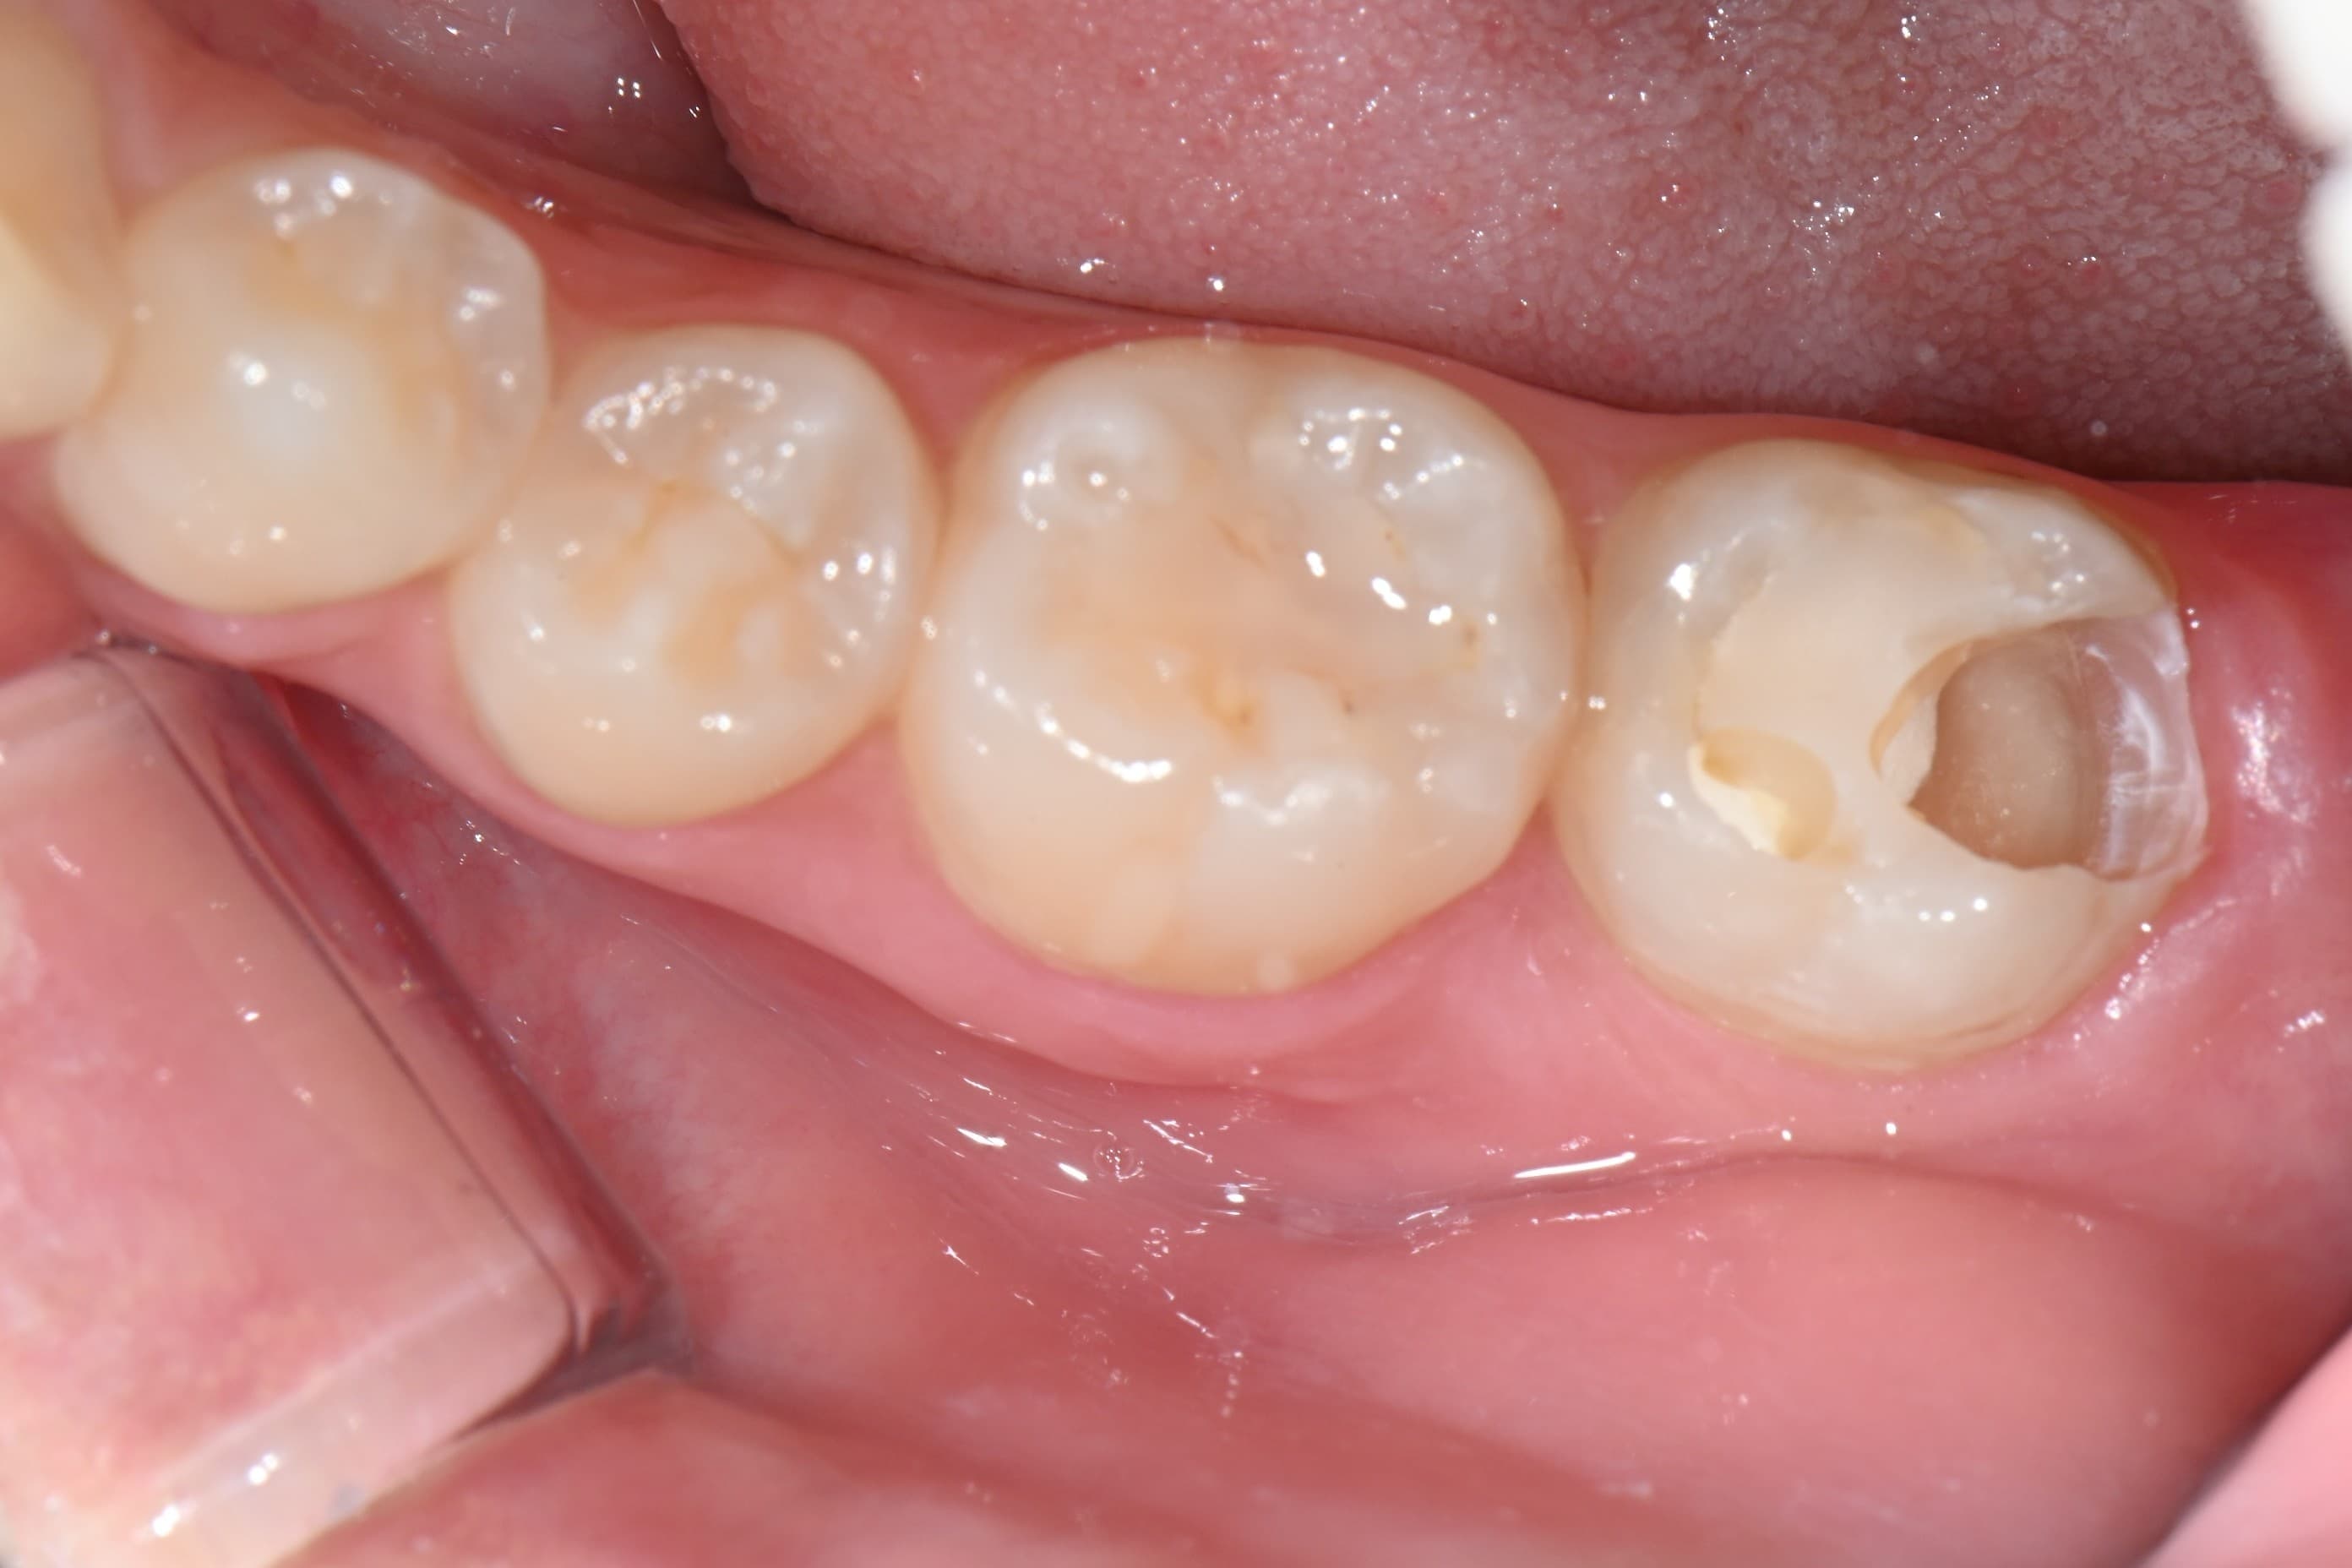

치료 완료

충치를 완전히 제거하고 자연 치아 색상의 레진으로 수복했습니다. 치아 형태가 깔끔하게 회복되었습니다.

충치 부위를 정밀하게 제거하고 자연 치아 색상의 레진으로 깔끔하게 수복